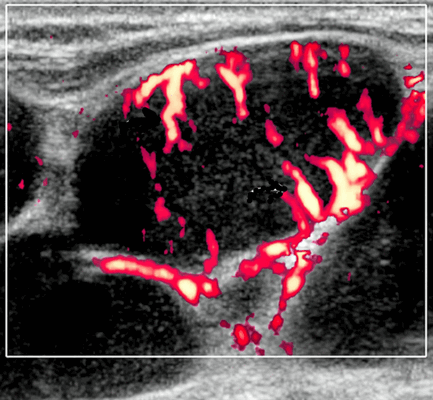

- Узловая неходжкинская лимфома (НХЛ): одиночные или множественные увеличенные яйцевидные внутрипаротидные лимфатические узлы, которые на УЗИ гомогенно гипоэхогенны по отношению к паренхиме околоушной железы, эхо-картина сетчатая. Заднее акустическое усиление. Выраженная внутриузловая гиперваскуляризация

Цветной допплер. Узловая НХЛ. Выраженная центральная или внутриузловая гиперваскуляризация. Паренхима при неходжкинской лимфоме более диффузная железистая гиперваскуляризация. Васкуляризация от умеренной до выраженной в плохо очерченных образованиях.

- Цветной допплер: смешанная васкуляризация с выраженным сосудистым рисунком и наличием периферической васкуляризации. Периферическая сосудистая сеть редко встречается в узлах НХЛ

Цветовой допплер: смешанная сосудистая сеть с выраженными внутриузловыми сосудами и наличием периферической сосудистой системы. Одна только периферическая сосудистая сеть редко встречается в узлах НХЛ. Спектральный допплер: переменное интранодальное внутрисосудистое сопротивление, которое носит неспецифический характер.